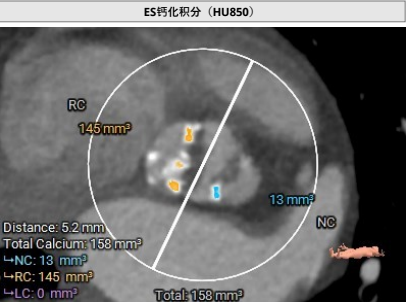

临床团队同时使用了Tavigator™进行术前影像学评估,配合医生手工描点评估。

主动脉瓣瓣环及其它基本平面测量

患者为71岁女性。瓣环圆化直径21.8mm,Type0型二叶瓣,瓣叶增厚轻度钙化。左侧冠脉开口高度13.1mm,右侧冠脉开口高度13.8mm,并且STJ高度可以达到22.3mm。投照角度推荐LAO8度/CRA8度。可行18mm球囊前扩,考虑到环上锚定,推荐0位植入Xcor™-23瓣膜,酌情后扩。